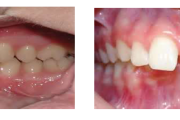

Ravijärgne seis. Jäävhammas on täielikult lõikunud.

) Röntgenülesvõte. Ülemise esimese jäävmolaari lõikumine on takistatud 2. piimamolaari tõttu

Esimese jäävmolaari ektoopiline lõikumine